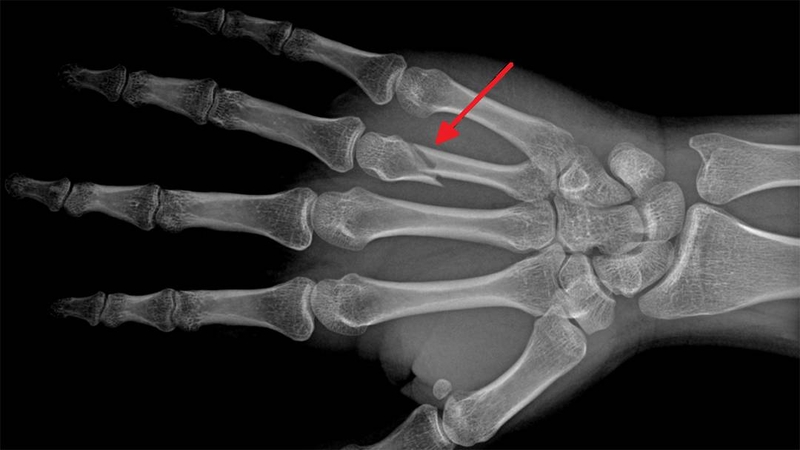

Tia X có thể tạo thành hình ảnh cơ thể con người trên màn hình hoặc phim dựa trên sự khác biệt về mật độ và độ dày của mô người. Do sự khác biệt này, khi tia X đi qua các cấu trúc mô khác nhau của cơ thể con người, chúng bị hấp thụ ở các mức độ khác nhau nên lượng tia X tới màn hình hoặc phim cũng khác nhau. Hình ảnh có độ tương phản đen trắng khác nhau được hình thành trên màn hình hoặc phim X-quang. Dựa trên sự tương phản đó, kết hợp với các biểu hiện lâm sàng, kết quả xét nghiệm và chẩn đoán bệnh lý, có thể đánh giá liệu một bộ phận nào đó trên cơ thể con người có bình thường hay không.

Ngay khi tia X được phát hiện đã cho thấy giá trị ứng dụng y học rất lớn, các nhà khoa học y tế đã sử dụng tia X để hiển thị chính xác vị trí gãy xương trên cơ thể con người. Theo thời gian, X-quang đã trở thành thiết bị không thể thiếu trong điều trị y tế hiện đại. Hiện nay, tia X không chỉ được sử dụng rộng rãi trong chẩn đoán và điều trị trong y học, trở thành vũ khí đắc lực giúp con người đánh bại bệnh tật mà còn được sử dụng cho các mục đích y tế không thể thiếu.